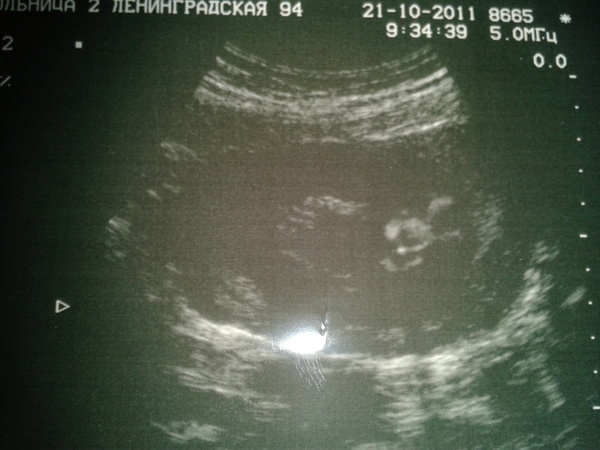

Встала на учет в жк на 10 неделе, куча анализов, узи, каждый прием у врача был очень волнителен, так как очень переживала за наше маленькое сокровище. На первом же узи нам сделали первое фото нашей малюськи и сказали что у нас будет девочка (папина мечта сбылась, он всю жизнь мечтал о дочке Даше)